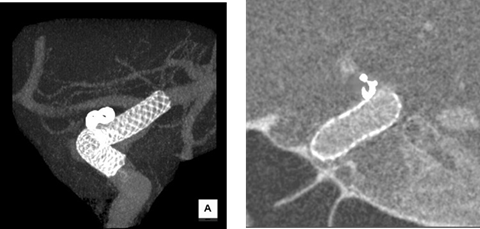

ステント留置術(FD留置後造影(MIP表示)・(MPR表示))